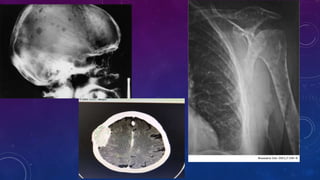

• Estadio: • Laboratorio •ECG Ecocardiograma • BMO( CTF, CTG, FISH, AP, IHQ) • Estudio de imágenes • Estadificacion: • Durie y Salmon: I; Hb >10g/dl Ca normal , Rx normal o Plasmocitario solitario, IgG <5000mg/dl IgA <3000mg/dl, Cadenalivianas en orina <4g/24hs. II; no I o III. III; Hb <8,5g/dl, Ca >12mg/dl, esiones osea avanzado[>4 lesiones osea y/o Fx patologica no vertebral ni costal], IgG >7000mg/dl, IgA >5000g/dl CL en orina >12g/24hs. A Crea <2mg/dl B >2mg/dl • ISS: I; B2MG <3,5mg/l y Alb >3,5 mg/dl II; no I oIII. III; B2MG >5,5mg/l • ISS-R: I; ISS I + LDH Normal, Ausencia de CTG de alto riesgo. II; No I o II. III; ISS III + t(4;14), t(14;16) o del (17p) o LDH elevado • Riesgo CTG • Alto riesgo(15%); t(14;16), t(14;20), del(17p), del 13q, monosomia 13, Cariotipo complejos • Riesgo intermedio(10%); t(4;14), Ganncia 1q • Riesgo estandar(75%); Hierdiploidia, t(11;14), t(6;14)